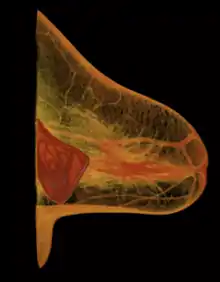

Breast-feeding

- Chest wall

- Pectoralis muscles

- Lobules

- Nipple

- Areola

- Milk duct

- Fatty tissue

- Skin envelope

The presence of breast implants currently presents no contraindication to breast feeding, and no evidence to support that the practice may present health issues to a breast feeding infant is recognized by the USFDA.

Women with breast implants may have functional breast-feeding difficulties; mammoplasty procedures that feature periareolar incisions are especially likely to cause breast-feeding difficulties. Surgery may also damage the lactiferous ducts and the nerves in the nipple-areola area.[112][113][114]

Functional breast-feeding difficulties arise if the surgeon cut the milk ducts or the major nerves innervating the breast, or if the milk glands were otherwise damaged. Milk duct and nerve damage are more common if the incisions cut tissue near the nipple. The milk glands are most likely to be affected by subglandular implants (under the gland), and by large-sized breast implants, which pinch the lactiferous ducts and impede milk flow. Small-sized breast implants, and submuscular implantation, cause fewer breast-function problems; however, it is impossible to predict whether a woman who undergoes breast augmentation will be able to successfully breast feed since some women are able to breast-feed after periareolar incisions and subglandular placement and some are not able to after augmentation using submuscular and other types of surgical incisions.[114]